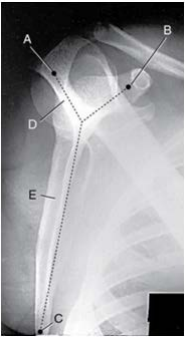

Analisar a imagem abaixo:

A imagem faz referência à incidência: